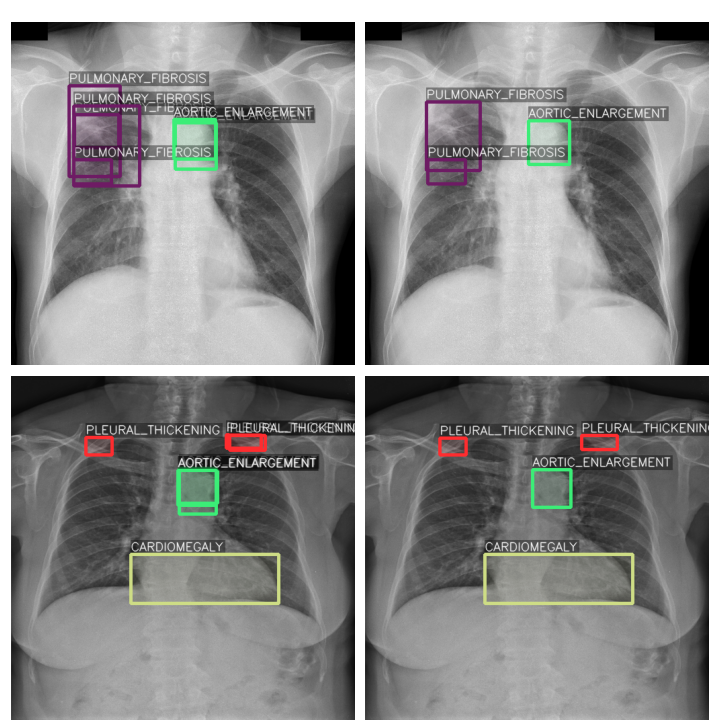

Each image can have one or more labels from multiple experts, and these labels often overlap. To produce the least noisy labels, we average overlapping bounding boxes of the same class into one bounding box. To determine if two boxes are overlapping, an intersection-over-union (IoU) threshold of 20% is used. This approach is based on weighted boxes fusion described in [15] but modified such that each bounding box has equal weight and confidence since they were manually labeled by an expert. An example of fused bounding boxes is shown in Fig. 1.

Refer to caption

Figure 1: Examples of bounding box averaging. The images on the left show the original bounding boxes, while the images on the right show fused bounding boxes which are used in our experiments.